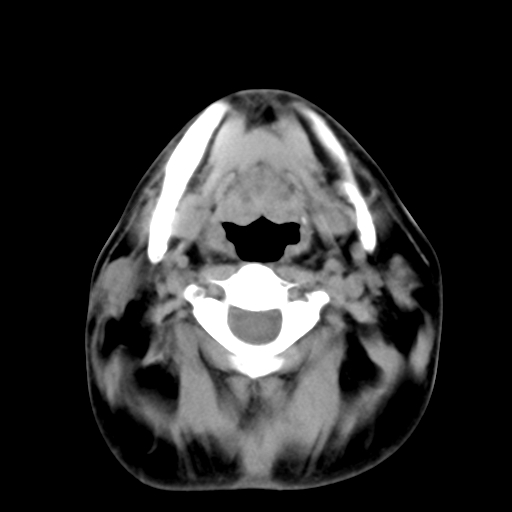

标题: CT24019:男,45岁,发现颈部肿物5个月。 [打印本页]

男,45岁,发现颈部肿物5个月,彩超示:双侧颈部及下颌部软组织增厚。

考虑双侧颈项部良性对称性脂肪增多症。